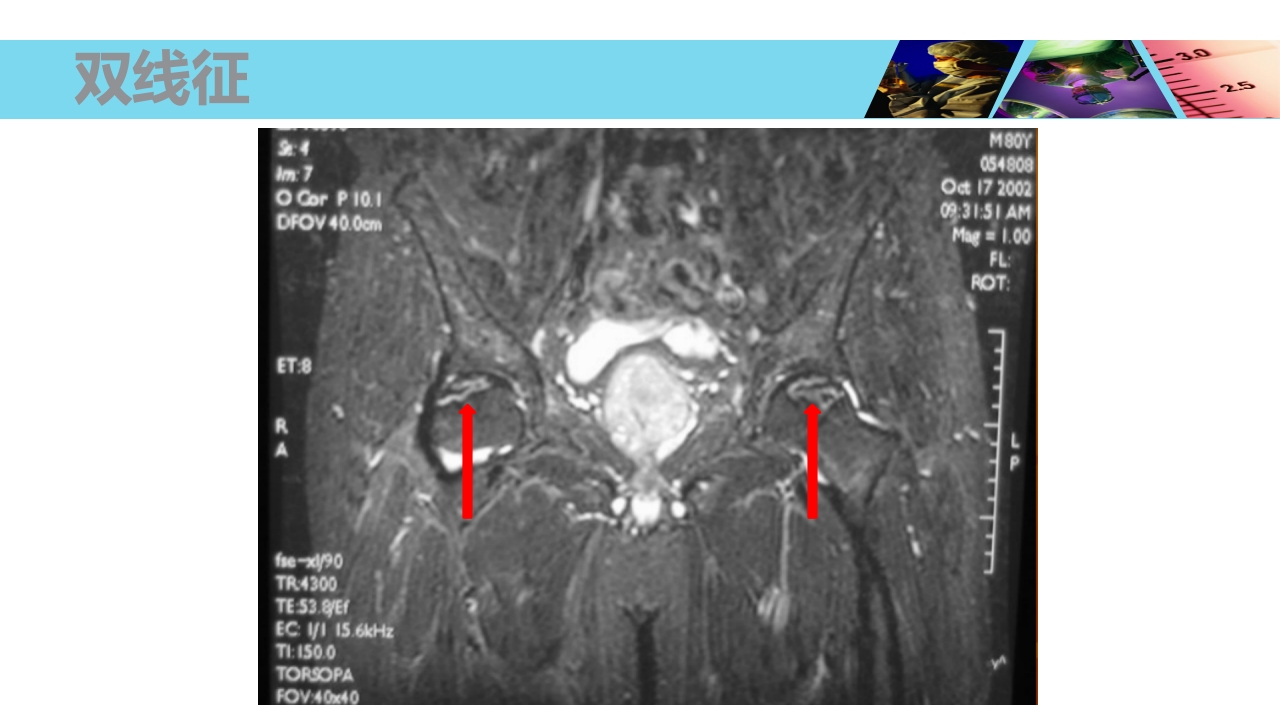

股骨头无菌性坏死 Necrosis of Femoral Head xxxx医院 骨科 WHO/WHAT/WHY/HOW? OUTLINE 1 2 3 4 5 概念及流行病学 病因 发病机制及病理 临床表现及诊断 治疗 概 念 Concept 股骨头坏死、股骨头缺血性坏死、股骨头无菌性坏 死等(Necrosis of Femoral Head) 不同病因破坏了股骨头血供所造成的最终结果。 损伤-修复(Damage-Repair) 4 股骨头血供 由旋股内、外侧动脉所发出的支持带动脉,占股骨头血供的70%。 股深动脉所发出的股骨滋养动脉,占股骨头血供的25%。 闭孔动脉或旋股内侧动脉所发出的股骨头韧带动脉,占股骨头血供的5%。 股骨头血供 一、流行病学 Epidemiology 世界骨科三大难题之一 在美国,年人均发生率在 2 万 -3 万之间,约有 5%-12% 的髋关 节置换...